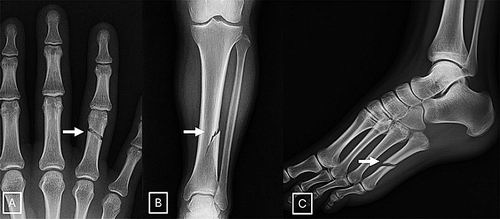

AI生成的X光片让科学家感到担忧。图片来源:北美放射学会

该研究设计了一项互动测试,旨在教会研究人员辨别AI生成的X光扫描图像与真实图像。它涵盖了AI生成的放射影像的一些典型特征,如骨骼过于光滑、脊柱异常笔直等。研究人员指出,除了培训放射科医生,数字水印等技术可以使识别真实图像变得更容易,政府机构主导的监管框架也可以这样做。(王铄)